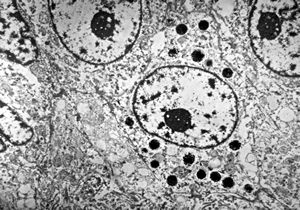

F,69y. | cystadenoma (Warthin tumor) … caruncula - (modified mitochondria in an autolysed sample)